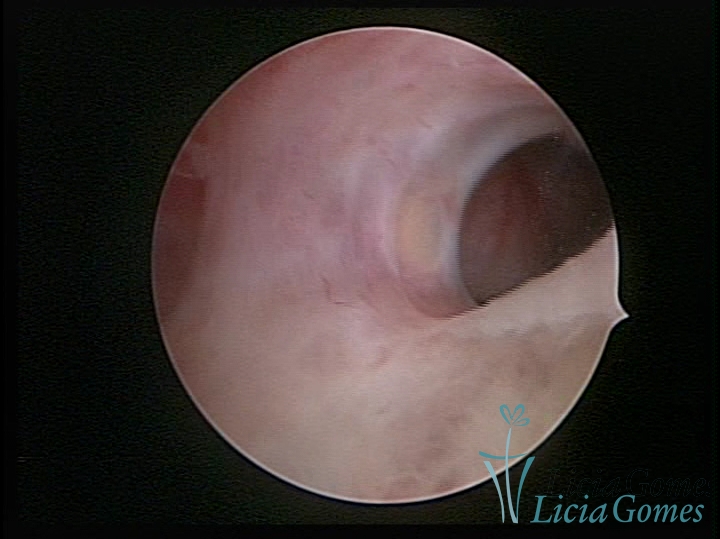

FIBROUS SYNECHIA

Uterine synechiae are scars (adherence) between the surface of the uterine walls, which may occur after the surgical procedure, uterine curettage, or after an inflammatory process in the uterine cavity (endometritis), which may lead to menstrual changes, infertility and obstetric complication such as abortion and premature birth.